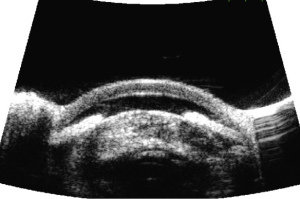

Phacomorphic Glaucoma is diagnosed by the presence of eye pain, history of decreased vision, evidence of mature cataract formation (slit lamp exam), angle closure (gonioscopy), and elevated intraocular pressure (applanation tonometry) in the affected eye. Distinguishing factors between primary angle-closure and phacomorphic angle-closure are presence of an intumescent cataractous lens and presence of cell and flare. Axial length measurement (usually short in phacomorphic) and records of the refraction may also be helpful in distinguishing between the two conditions .[2][4][5][6] In primary angle-closure the fellow eye has shallow anterior chamber, but in phacomorphic glaucoma the fellow eye usually has normal anterior chamber depth or pseudophakia. Ultrasound biomicroscopy (UBM) can assist in the diagnosis and may show a dense cataractous lens causing mass effect on the iris with anterior bowing and closed angles (Figure 1).